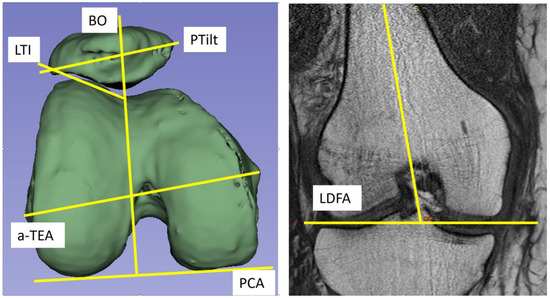

| TKA | Total knee arthroplasty |

| TKR | Total knee replacement |

| LDFA | Lateral distal condylar angle |

| PCA | Posterior condylar angle |

| PTilt | Patella tilt |

| LTI | Lateral trochlear angle |

| BO | Bisect offset |

| TEA | Transepicondylar line |

| a-TEA | Anatomical transepicondylar line |